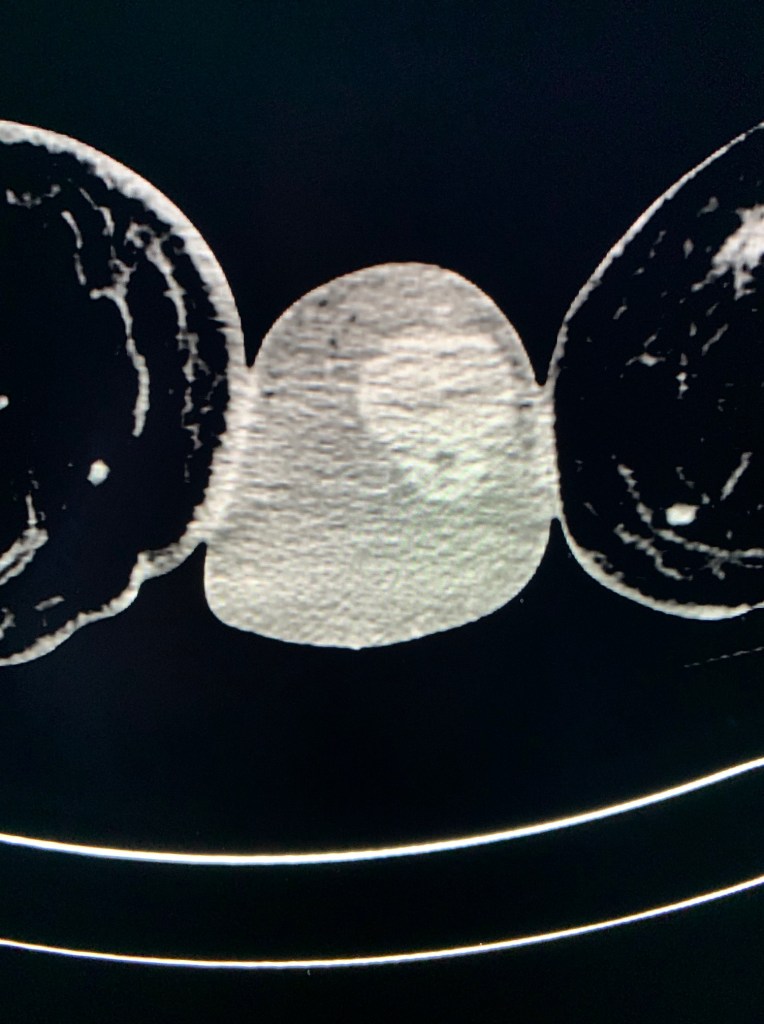

Axial CT image through the proximal penis with surrounding scrotal edema. The mouth is the urethra within the corpus spongiosum. The eyes are the cavernosal arteries within the paired corpora cavernosa.